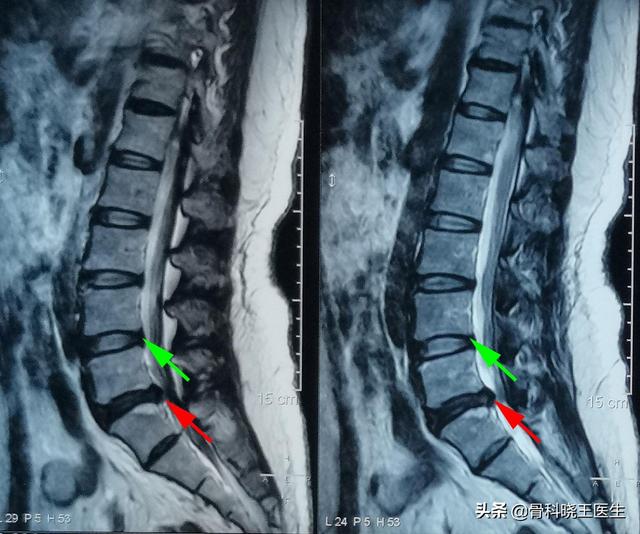

Les hernies discales légères à modérées peuvent très bien se rétablir, mais les hernies graves sont difficiles à traiter car une fois qu'une hernie grave s'est développée, cela signifie que le nucleus pulposus au centre du disque a traversé l'anneau fibreux au niveau du bord postérieur et même le ligament longitudinal postérieur, ce qui rend la guérison très difficile avec le temps. Ci-dessous, l'image tomodensitométrique d'un patient souffrant d'une hernie discale grave :

Récemment, une patiente de 60 ans, de sexe féminin, a été prise en charge. Elle s'est rendue à l'hôpital pour un examen, un prolapsus discal lombaire, du point de vue de l'imagerie, le problème est plus sérieux. Cependant, après avoir communiqué avec la patiente, celle-ci s'est plainte qu'elle n'osait pas se tordre le dos, que ses activités étaient limitées, qu'elle était mal à l'aise après avoir marché pendant longtemps et qu'elle faisait habituellement des travaux ménagers à la maison tous les jours. Après examen, il s'est avéré que les symptômes du décollement lombaire n'étaient pas évidents, mais que le claquage du muscle lombaire et du muscle érecteur de la colonne vertébrale était plus grave. La cause de la douleur est due à l'étirement à long terme des muscles lombaires de la bascule pelvienne. Après trois massages et un ajustement de la posture, la posture de marche causée par la bascule pelvienne s'est améliorée de façon très évidente et on peut dire que les symptômes ont complètement disparu.